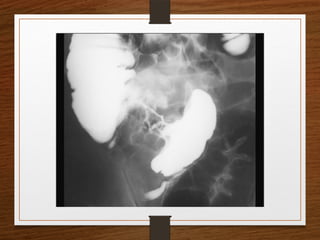

Contrast enema

• Features seen at the point of torsion include a

smooth, curved tapering of the colonic lumen, like a

hooked beak (the bird of prey sign)

• the mucosal folds often show a ‘screw’ pattern at the

point of twist